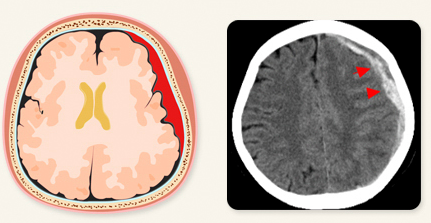

급성 경막하 출혈은 뇌 주변의 경막 내부에서 혈관이 외상으로 인해 파열되어 발생하는 출혈을 의미합니다. 이러한 출혈은 주로 뇌 실질의 좌상(타박상)이나 파열, 뇌내출혈을 동반하며, 경막하 공간에 피가 고여 뇌를 압박하여 심각한 증상을 유발할 수 있습니다.

급성 경막하 출혈의 원인과 진단: 낙상, 교통사고, 폭행 등의 외상이 주된 원인이며, 항응고제 복용이나 과음과 같은 위험 요인도 출혈 가능성을 높일 수 있습니다. 진단은 뇌 전산화 단층촬영(CT)을 통해 이루어지며, 출혈량과 뇌부종 정도를 확인하여 치료 계획을 세우는 데 중요한 역할을 합니다.